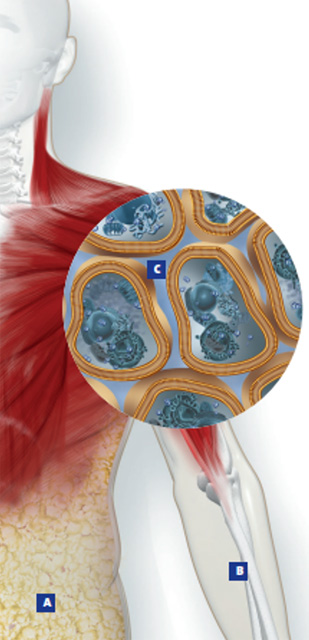

A = Fettmasse

B = Fettfreie Masse inkl. Body Cell Mass

C = Wasserverteilung intra- und extrazellulär